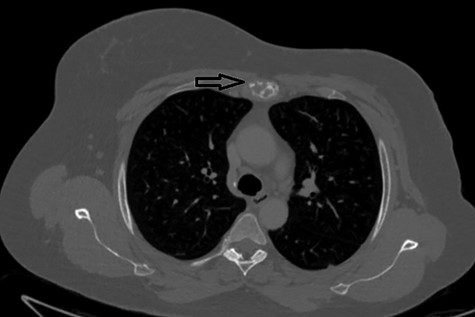

The second case at our institution was a 52-year-old woman with a history of left breast carcinoma treated for which she had undergone left wide local excision and sentinel node biopsy. Due to uncertainty regarding margins, she required a re-resection of her left breast tissue. She completed adjuvant radiotherapy and received maintenance hormonal therapy. She presented 8 months following her radiotherapy with sternal pain and positron emission tomography–computed tomography (PET–CT) imaging demonstrated localized uptake within the sternum (Fig. 3). Biopsy demonstrated proven recurrence of metastatic breast cancer. She was seen in clinic and counselled for partial sternectomy and reconstruction. She underwent partial sternectomy and underwent reconstruction with Synthes® plates. Her post-operative recovery was unremarkable. Post-operative histology was consistent with metastatic breast carcinoma, which was completely excised. The patient made an uncomplicated recovery and was seen in the outpatient clinic with a satisfactory post-operative chest radiograph (Fig. 4).